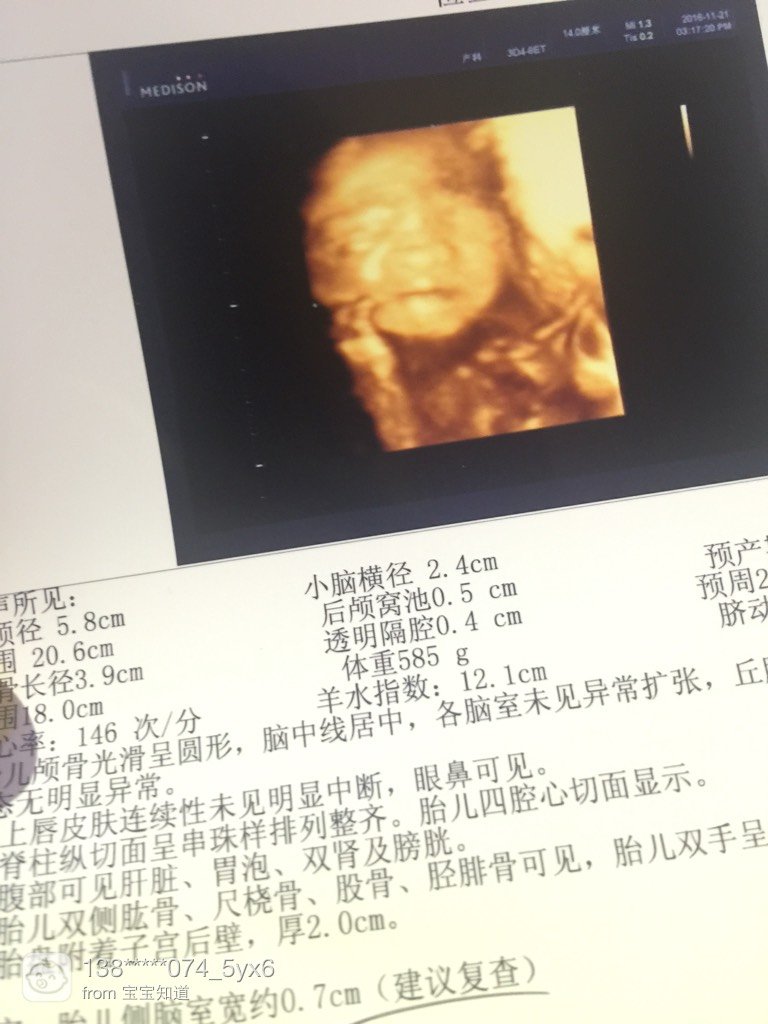

大脸宝宝!!!

脸这么大,一看串导就是宝婚像我生昌室喽!